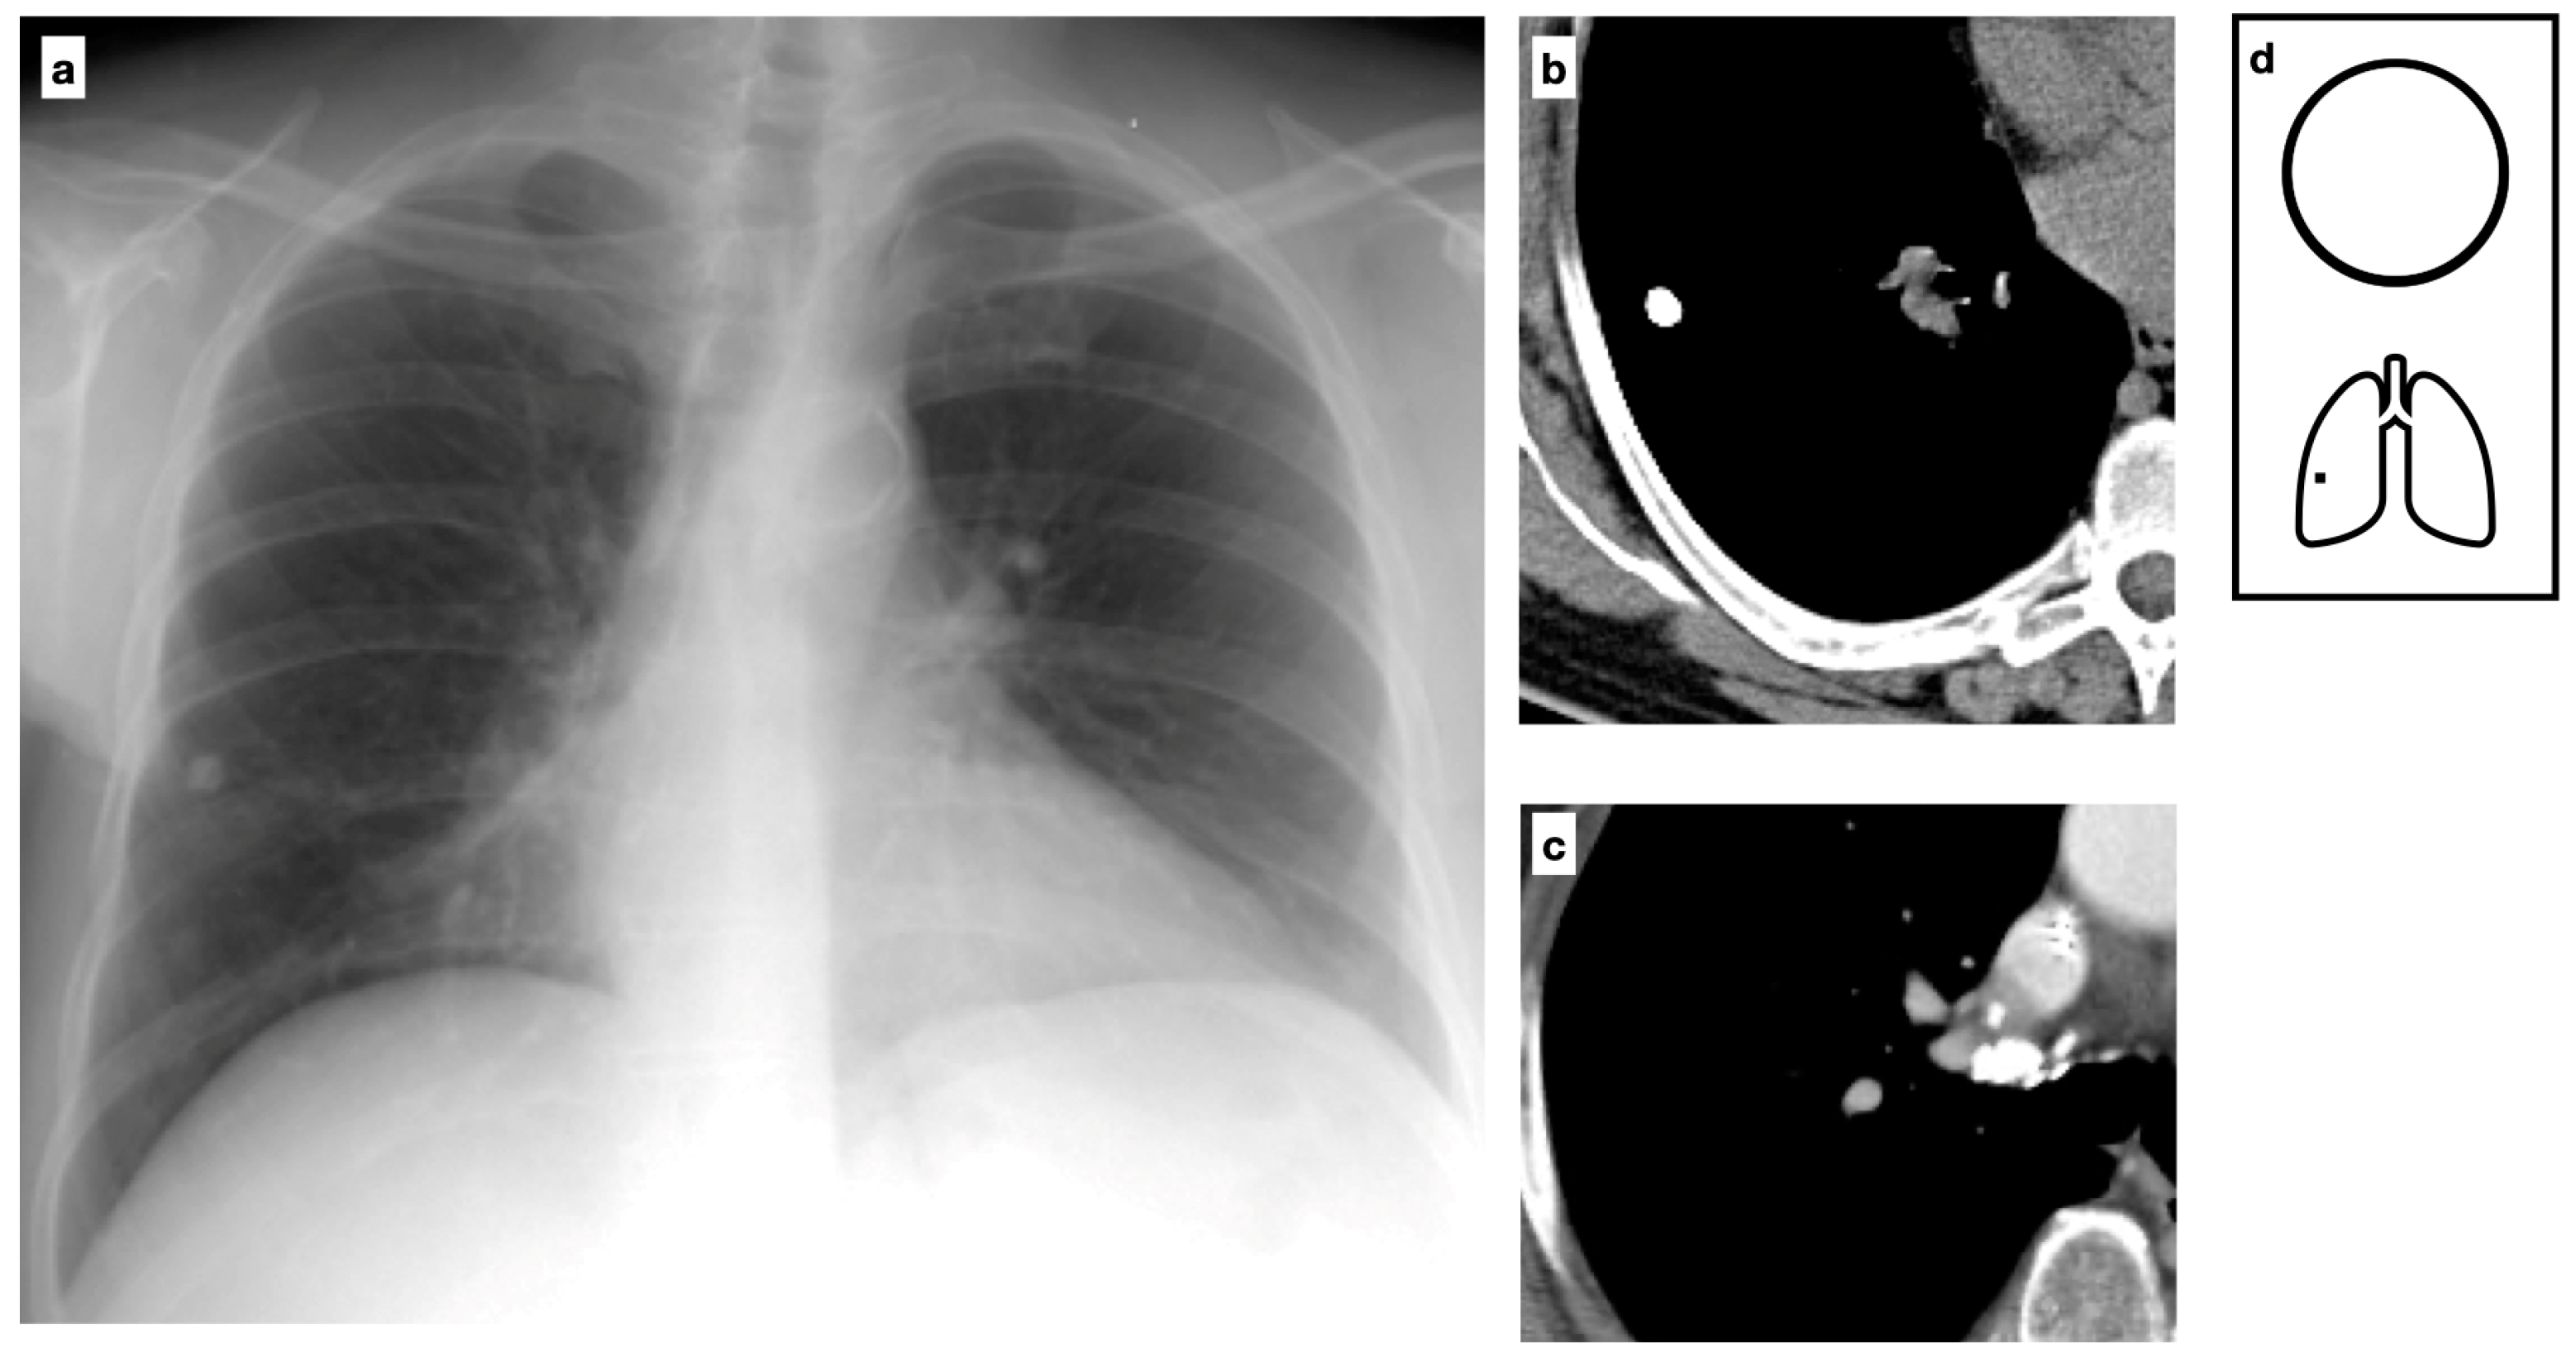

Figure 10.

CT demonstrates diffuse calcified nodules in a patient with osteosarcoma (a,b) (Courtesy of M. Mereu). Bone formation and ossification in osteosarcoma and chondrosarcoma can result in calcified metastatic nodules of the lung. Pattern of calcification (c).